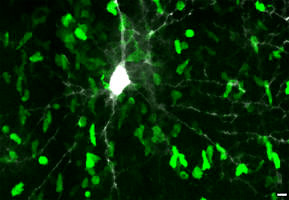

Erlanger Forschende untersuchten Entzündungen im Fettgewebe Wissenschaftlerinnen und Wissenschaftler des Mikrobiologischen Instituts – Klinische Mikrobiologie, Immunologie und Hygiene des Universitätsklinikums Erlangen und des Trinity College Dublin haben einen Faktor entdeckt, der möglicherweise die Entstehung der Fettleibigkeit begünstigt. Es wurde untersucht, wie Immunzellen im Fettgewebe zusammenarbeiten und dabei Entzündungen verursachen, die wiederum zu Gewichtszunahme und Fettleibigkeit […]Erlanger Forschende untersuchten Entzündungen im Fettgewebe Wissenschaftlerinnen und Wissenschaftler des Mikrobiologischen Instituts – Klinische Mikrobiologie, Immunologie und Hygiene des Universitätsklinikums Erlangen und des Trinity College Dublin haben einen Faktor entdeckt, der möglicherweise die Entstehung der Fettleibigkeit begünstigt. Es wurde untersucht, wie Immunzellen im Fettgewebe zusammenarbeiten und dabei Entzündungen verursachen, die wiederum zu Gewichtszunahme und Fettleibigkeit […]